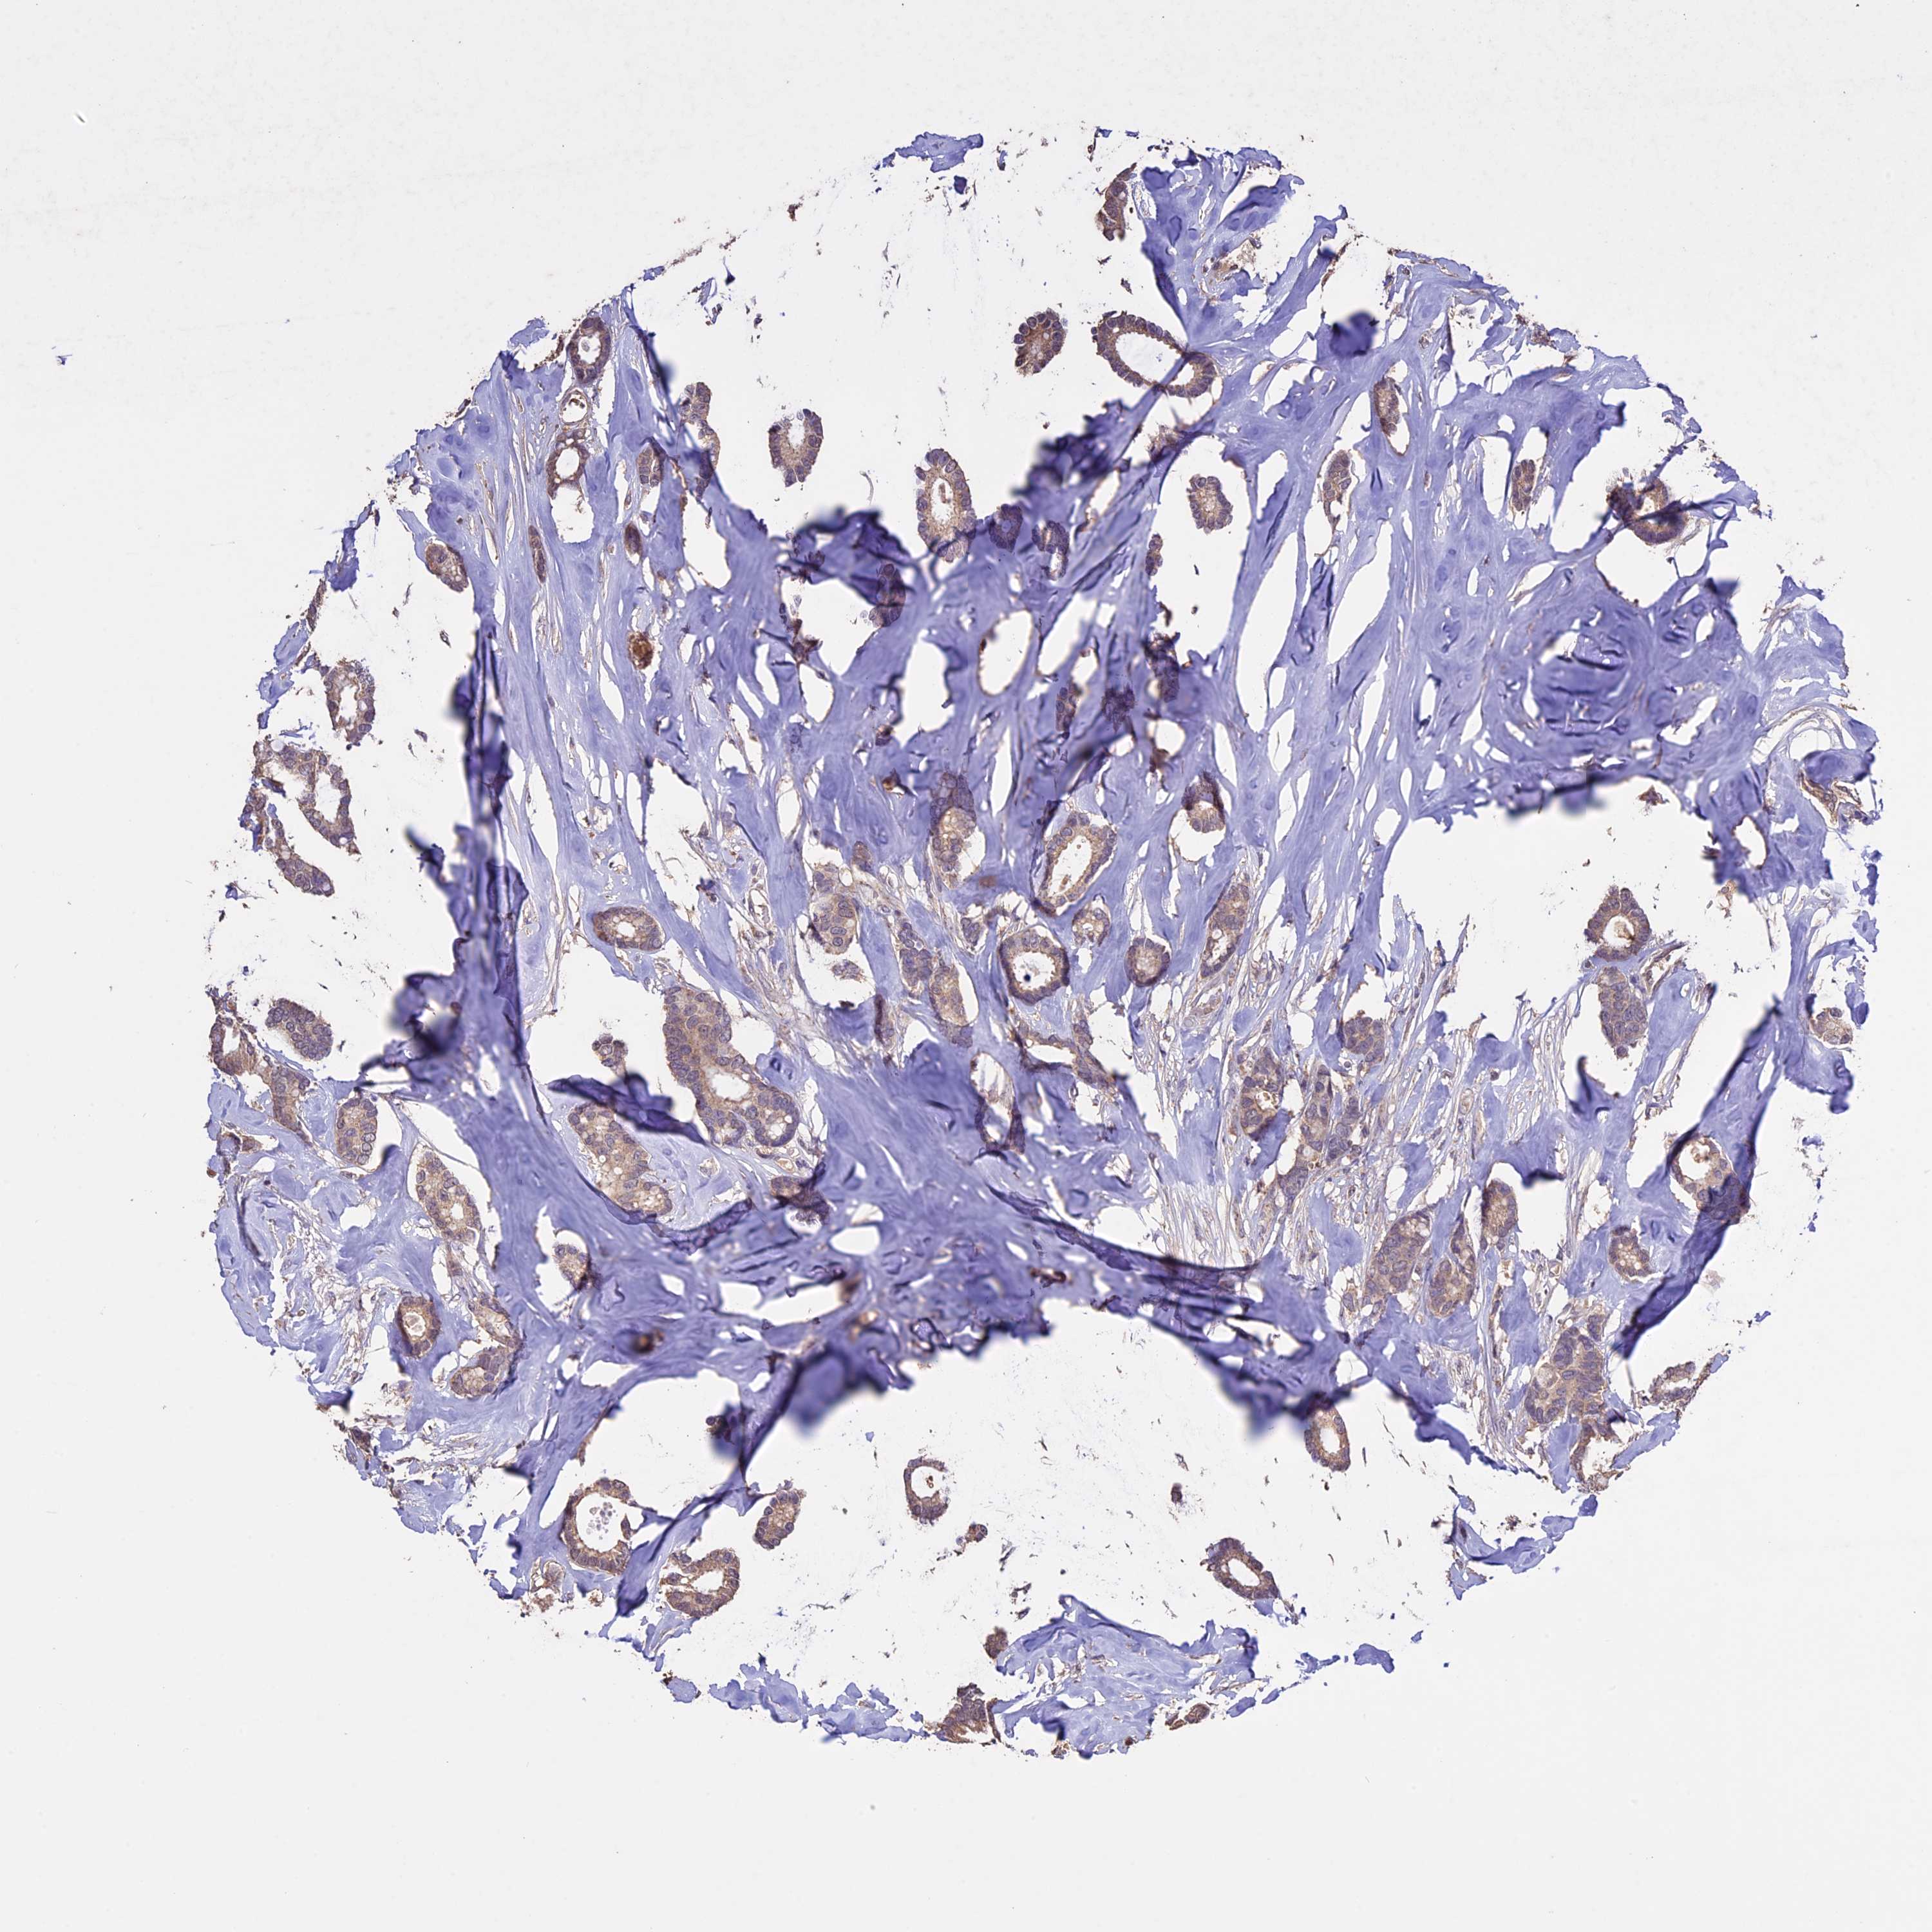

CANCER BREAST CANCER Show tissue menu

BRCA TCGA BRCA VALIDATION PROTEIN EXPRESSION